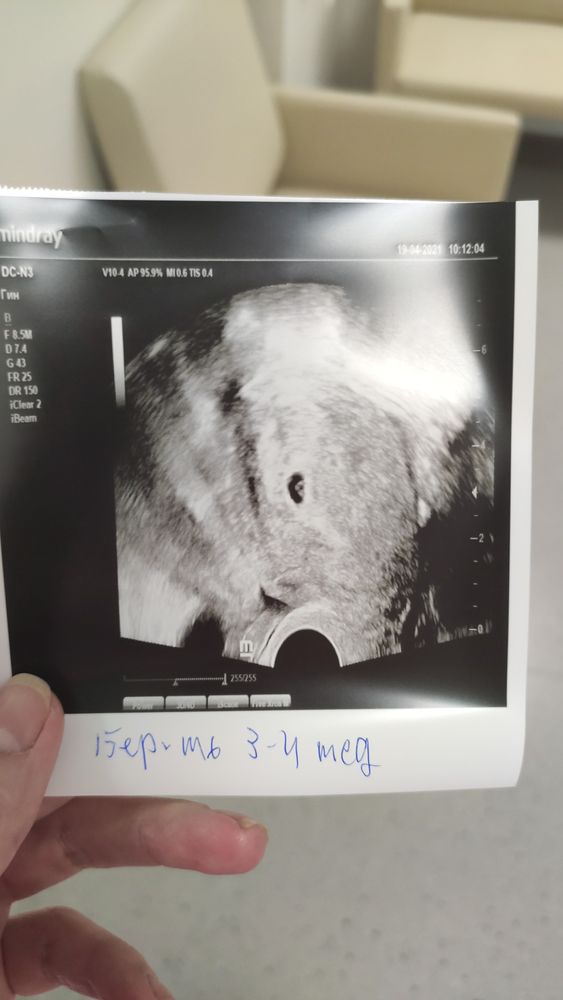

19 дпп. Первое УЗИ.

Я БЕРЕМЕННА !Ну вот я и сходила на узи. 🤗 СБ нет.рано.увидели одно ПЯ. Подсаживали двух 5 дневок отличников. РЕ сказала через недельки полторы на узи. Возможно второй прячется. Посмотрим) рада и одному и двум не расстроюсь.😊 8 лет не получалось а тут с первого раза🥰

наше первое фото.единственное не спросила размер ПЯ. А цифры на снимке не понимаю(

19.04.2021